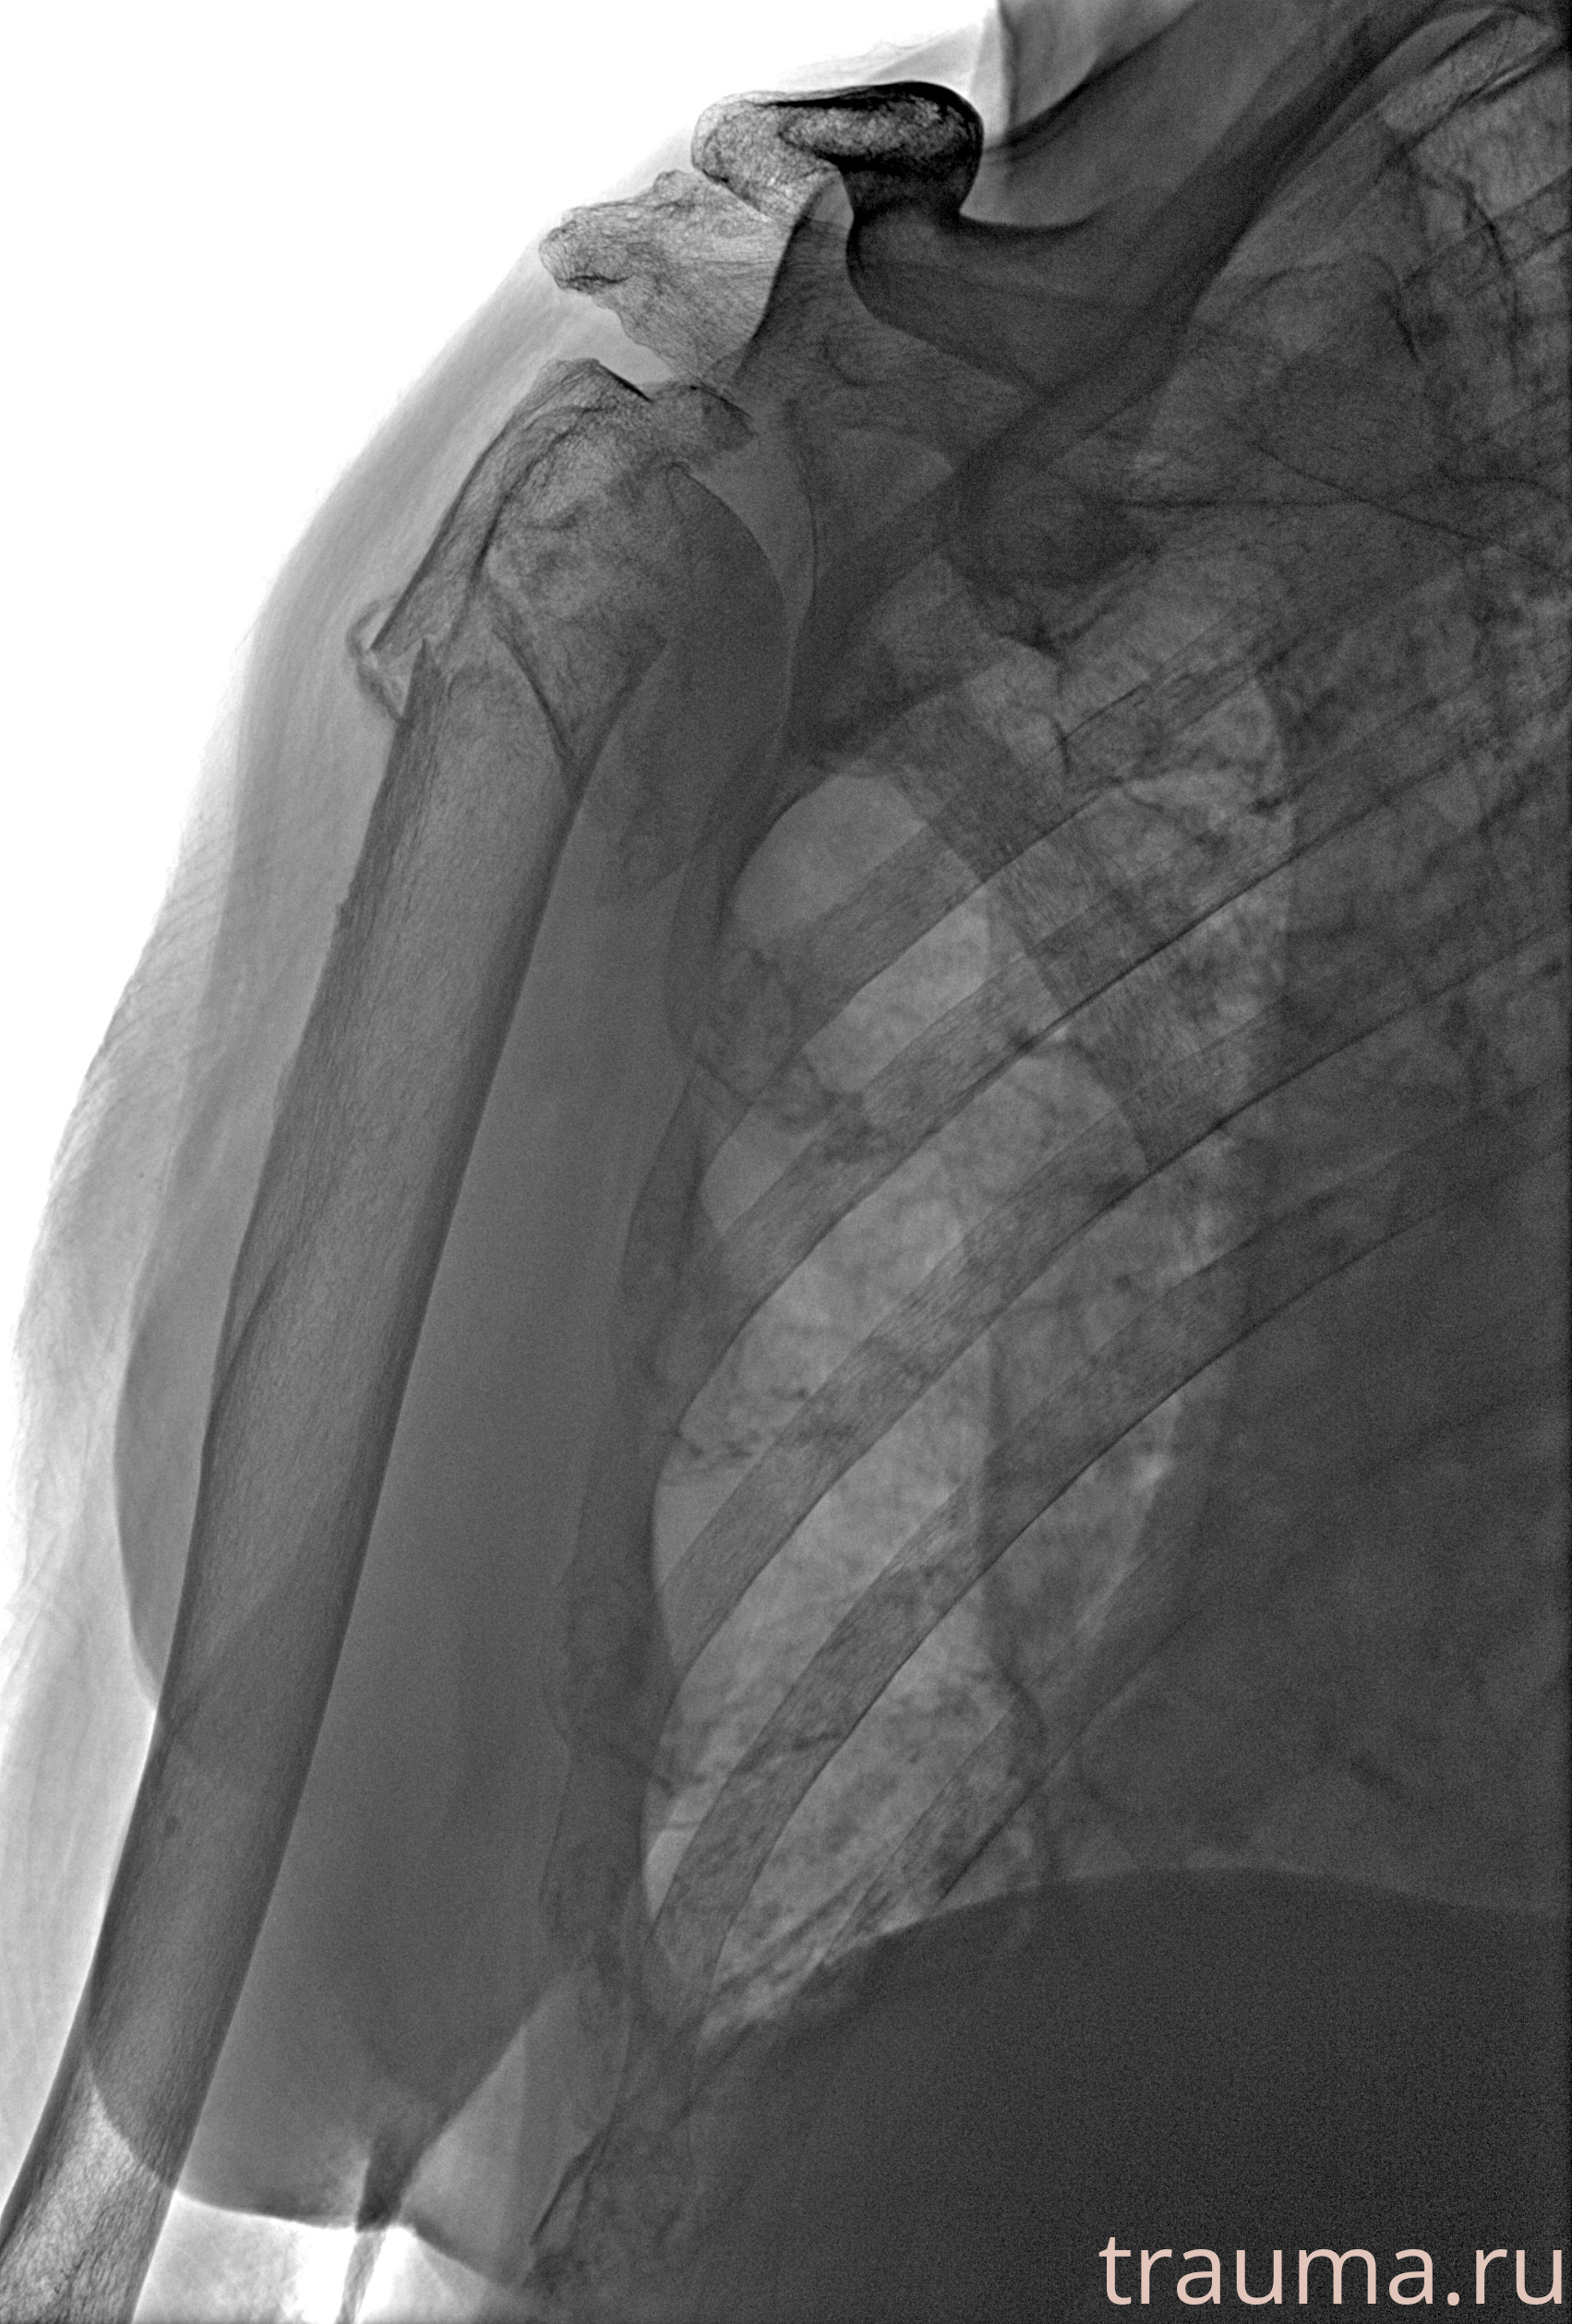

Рентгенограммы

Рентген на дому: по вашему адресу приезжает врач-рентгенолог, травматолог-ортопед с мобильным рентгеновским аппаратом, проводит диагностику травмы или заболевания, делает необходимые рентгенограммы, дает рекомендации по дальнейшему лечению. Получить качественные снимки в домашних условиях возможно благодаря уникальной методике, разработанной МосРентген Центром для института  Склифосовского